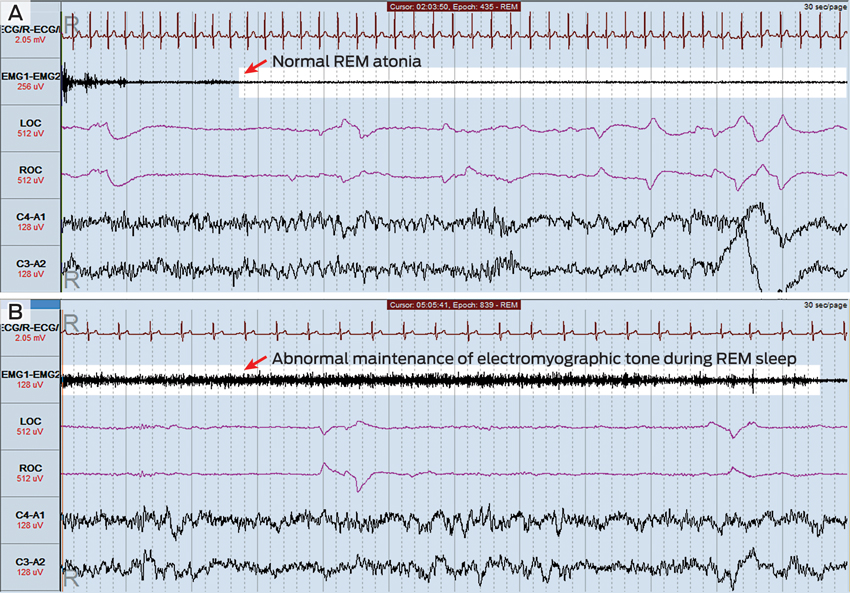

The patient underwent overnight laboratory-based polysomnography (Figure) with video monitoring. Total sleep time was 404 minutes, with a normal sleep efficiency (time asleep ÷ time in bed) of 85.7%, a normal arousal index of 9.3 events/hour and a normal apnoea–hypopnoea index of 0.7 events/hour. Minor periodic limb movements were detected but were not associated with electroencephalographic arousals.

During periods of rapid eye movement (REM) sleep, abnormal motor activity was detected (Figure, B). Muscle tone, as measured by electromyographic tone, actually increased during some periods of REM sleep, and phasic limb movements were seen during these periods. The patient thrashed his arms around on a number of occasions during REM sleep, but no other violent motor activity was detected. There was no evidence of seizure activity on the electroencephalogram recording. The polysomnography findings were thought to be consistent with a diagnosis of REM sleep behaviour disorder.

RBD can be idiopathic or associated with an underlying neuropathological condition, particularly the α-synucleinopathies Parkinson disease, Lewy body dementia and multisystem atrophy.4 Up to 65% of patients with RBD develop one of these conditions after a variable lag period, which is sometimes measured in decades.5 In addition, RBD is diagnosed in significant numbers of patients with a known α-synucleinopathy.6 Arousals during REM sleep due to obstructive sleep apnoea can mimic features of RBD, making this an important differential diagnosis.7 Diagnosis of RBD requires suggestive clinical features and abnormalities detected on overnight polysomnography, particularly the maintenance of electromyographic tone during the REM stage of sleep and associated phasic limb movements.